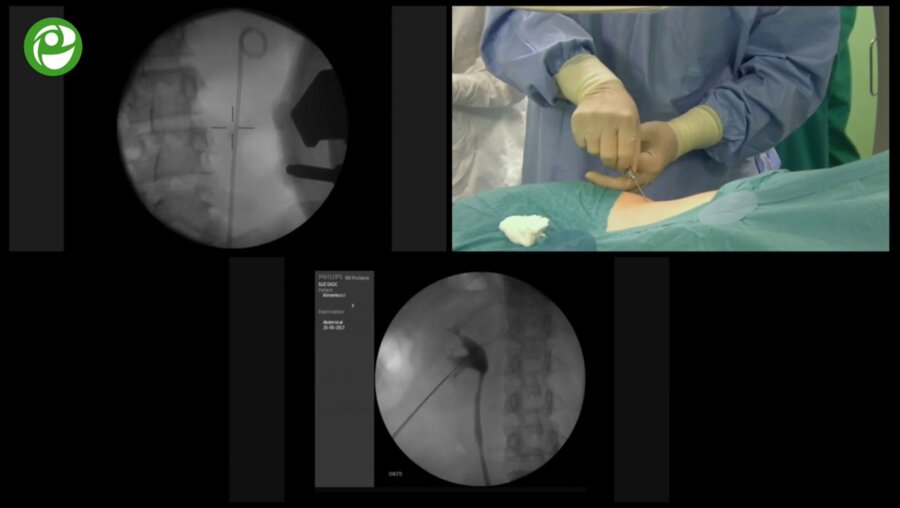

Операции на почках и надпочечниках